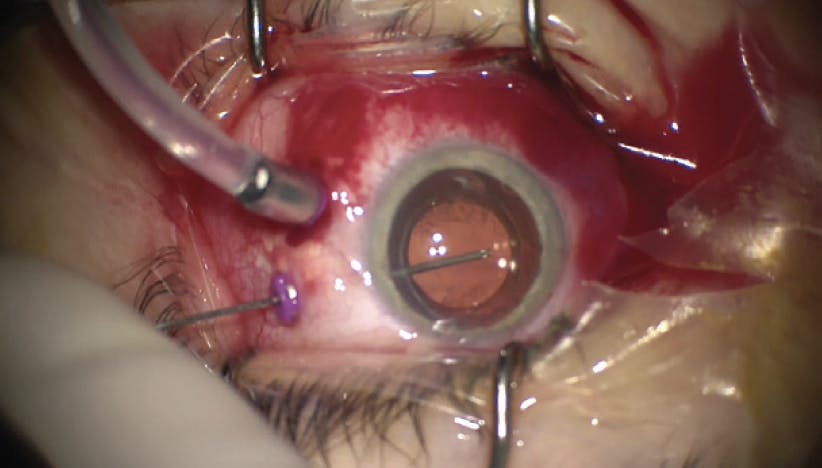

María H. Berrocal, MD

A 59-year-old patient presented with 20/50 VA complaining of floaters. Initial OCT revealed an epiretinal membrane (ERM; Figure 1) and clinical examination confirmed the presence of vitreous opacities (VOs). Notably, the patient did not complain of metamorphopsia.

Using 27-gauge instruments, a 3-port approach, and the NGENUITY 3D Visualization System (Alcon), I initiated vitrectomy to address the VOs that were observed in the anterior vitreous (Figure 2). As with all of my cases, I performed a close inspection of the periphery for any remaining vitreous. This is easiest with a 3-port approach.

After clearing vitreous, I peeled the ERM (Figure 3). Similar to my attention to detail regarding remaining vitreous in the posterior segment, I am careful to remove all observable pieces of ERM. Remaining ERM tissue could create postoperative visual disturbances, which would negate the effectiveness of removing VOs in the first place.